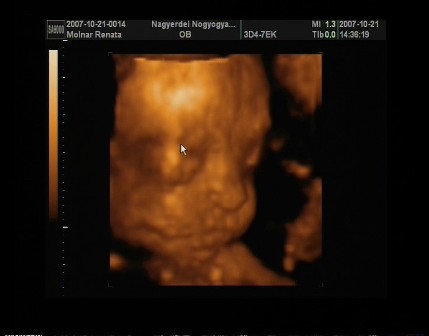

Egézséges kislányom lessz!Néhány fotó!!!! Kép Kép Kép Kép

m. reni